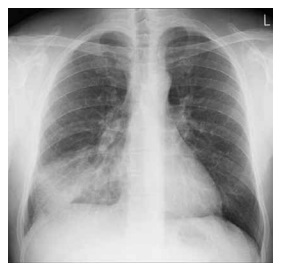

Além disso, observaram-se eletrocardiograma em

ritmo de fibrilação atrial, ausculta pulmonar com estertores

de base até terço médio bilateralmente, FR de 33 irpm,

edema bilateral de membros inferiores e estase jugular. Um

raio X do tórax está disposto a seguir.